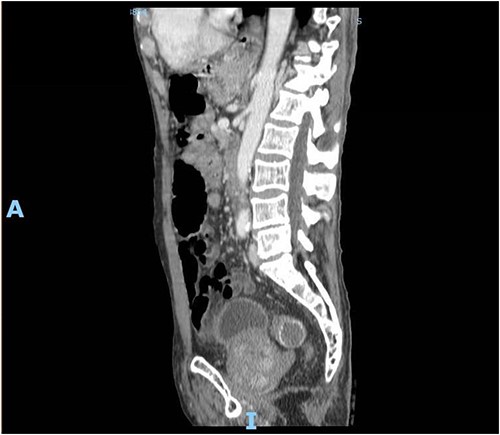

Upon clinical examination, the patient was vitally stable. Abdominal examination revealed a distended abdomen with generalized tenderness. Digital rectal examination revealed an empty rectum with no palpable masses. Laboratory investigations were unremarkable (Table 1). Abdominal X-ray was done (Fig. 2) and showed dilated large bowel loops suggestive of bowel obstruction. Enhanced CT scan of the abdomen and pelvis was obtained (Figs 3–5) and showed a dilated large bowel loop, with air fluid level. A 2.5-cm gallstone was noted, impacting the sigmoid colon and causing partial large bowel obstruction. There was evidence of pneumobilia with air foci within the gallbladder with a suspected fistula with the hepatic flexure.

Enhanced CT scan of the abdomen showing a gallbladder stone impacted at the sigmoid colon, with a significantly enlarged prostate causing narrowing of the rectosigmoid junction (sagittal view).